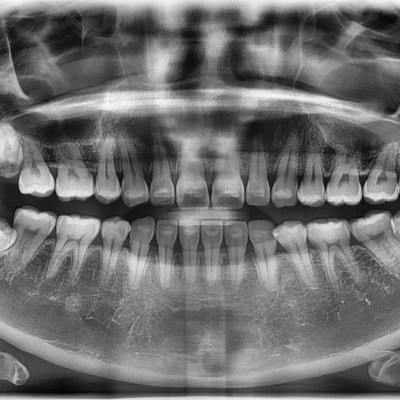

#28 사랑니 발치 구강 외과 전문의가 당일 발치했습니다. #28 사랑니 발치 구강 외과 전문의가 당일 발치했습니다. -----------------------------..

작성자 이턱이 작성일 03-12 조회 39